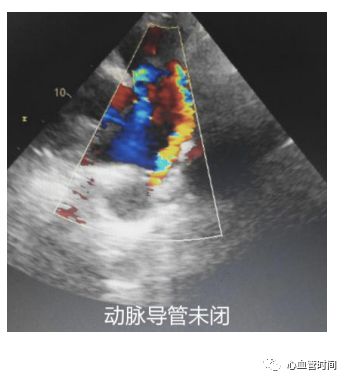

肺动脉观察肺动脉及分支内有无血栓、有无异常血流。在测量肺动脉速度时,若频谱形态出现异常,呈现 连续的不规整的形态时,要怀疑可能存在 动脉导管未闭,观察有无 自降主动脉发出、冲向肺动脉的花彩血流束。 左心耳在肺动脉长轴切面基础上,探头下压一点点可见左心耳,其与左心房一起形成了一个

倒置句号的形状,左心耳就是句号的小尾巴,可观察有无血栓或烟雾影。当然经胸心脏超声观察左心耳的可能性有限,对需仔细观察左心耳的患者,还需行